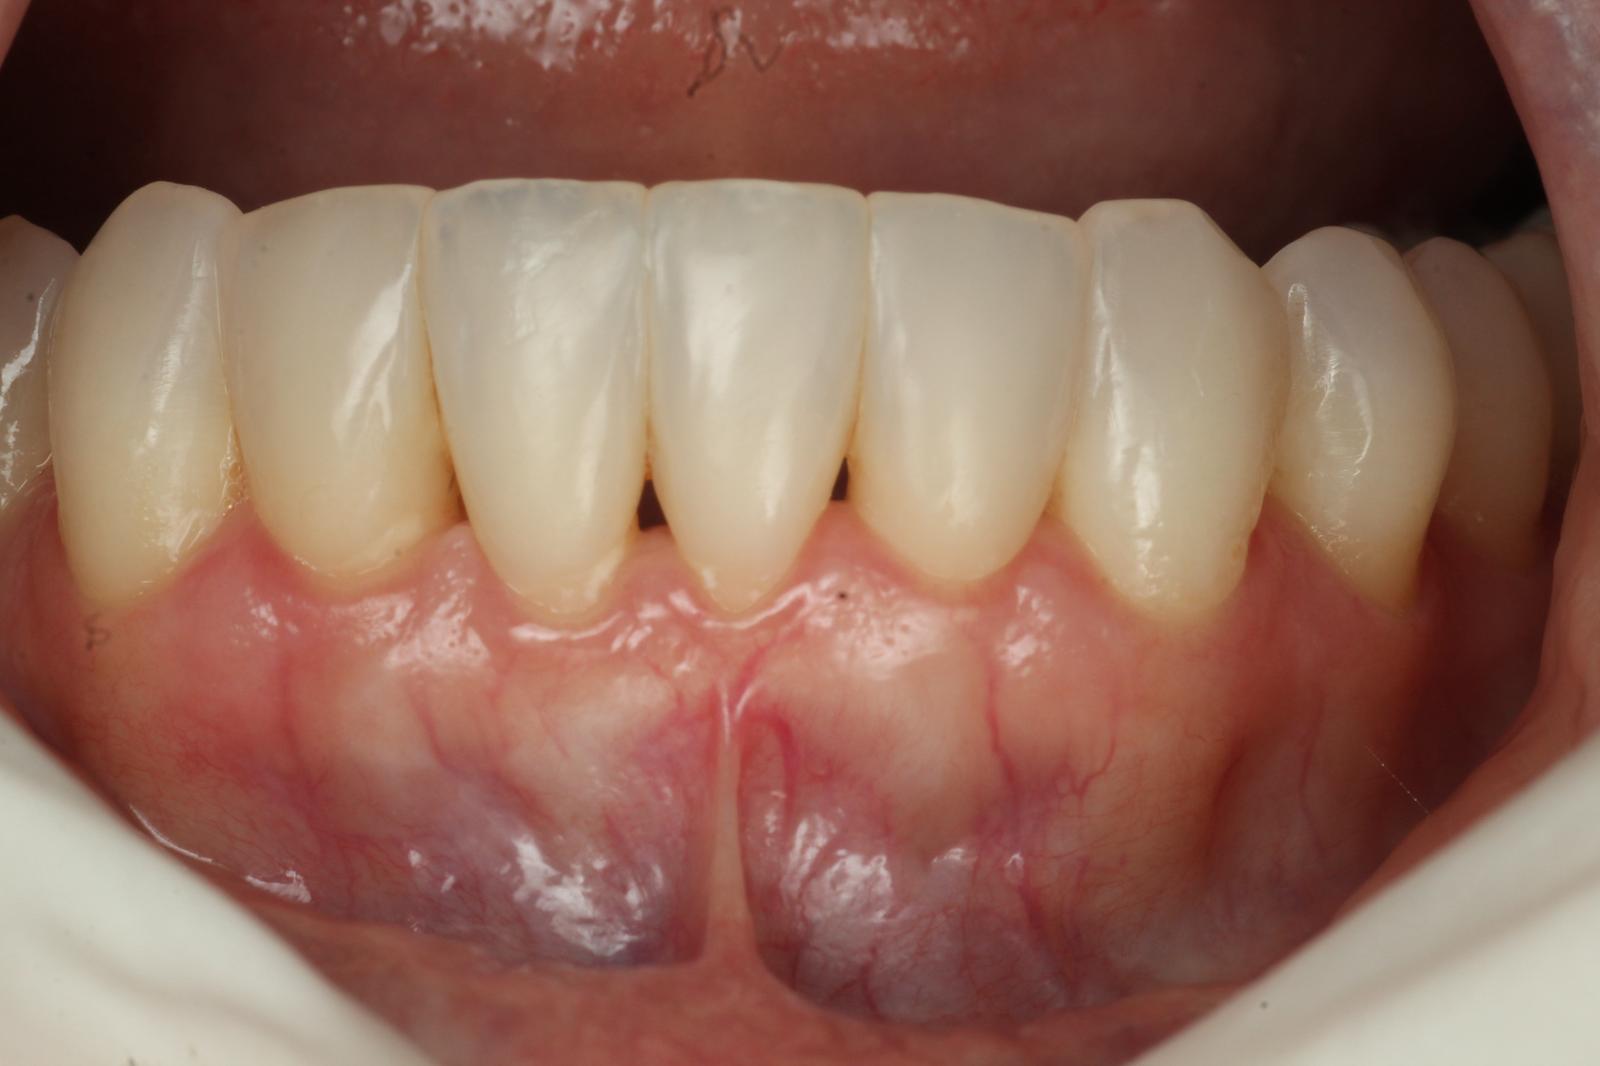

2.Gum Graft Surgery

In cases of gum recession, a gum graft can help restore protective tissue around the teeth. Tissue—often from the roof of your mouth—is grafted onto the affected areas, helping to reduce sensitivity, improve appearance, and prevent further recession.